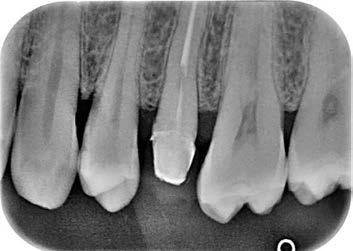

The canal was sealed with a Thermafil™ cone (Dentsply Sirona) with an apical diameter of 0.30 mm (Figs. 3-4).

Figure 3: Root canal therapy completed under proper isolation. Figure 4: Radiography of completed root canal therapy and reconstruction made completely in glass hybrid cement.

This element was not stimulated with the cold test and the radiographic image revealed an incomplete endodontic treatment (Figs. 1-2). The element seemed to present a suitable root length for a conservative restoration, but the apical position of the carious lesion and the proximity of the interdental bone ridge didn’t allow a correct rehabilitation with prosthetic crown, respecting the biological width.2